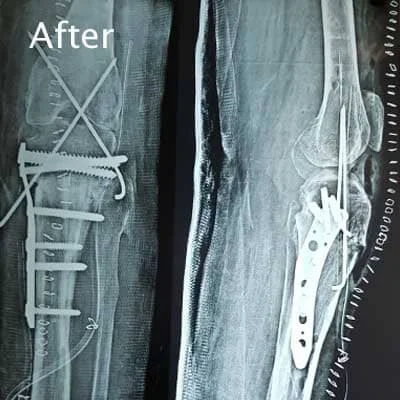

Complex Orthopaedic Surgery